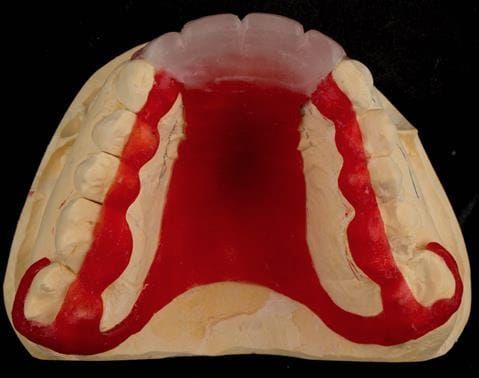

- Extract the upper 2-2 teeth and replace with an interim acrylic based partial denture. Reline the interim denture over 9 - 12 months, replacing with a definitive cobalt chromium based partial denture. The definitive denture would ideally be designed as an occlusal protective splint to reduce the the potential for mechanical wear and breakages of the moderately/heavily restored maxillary dentition. In addition, should further upper teeth require extraction they could be added on to the denture cobalt chromium framework - therefore a new prosthesis would not be required as future teeth are lost. This option would produce an excellent aesthetic outcome. This is the option the patient chose to have.

Following consultation and second discussion appointment the patient chose to have option 3 namely, a maxillary cobalt chromium based partial denture/protective occlusal splint. The clinical situation and treatment process is shown in detail below with photographs. The patient was successfully rehabilitated with this and her quality of life considerably improved. The clinical work was provided by Finlay and the technical work by Rowan.